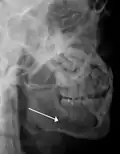

3D CT reconstruction of mandible fracture, white arrow marks fracture, red arrow marks moderate displacement and open bite -